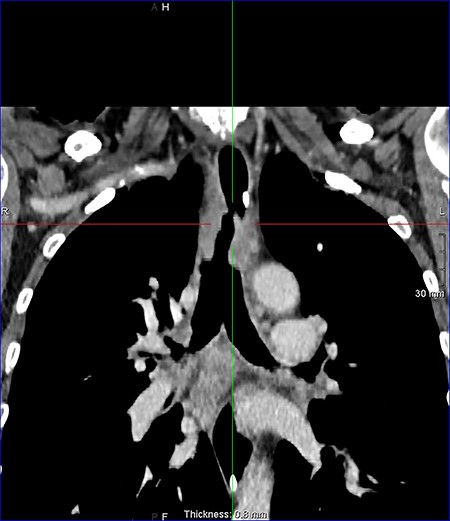

On examination, the patient had no obvious abnormality in the valve puncture. The stoma site was normal except for some crusting around the edges. A marked abnormality on the tracheal wall ~6 cm inferior to the stoma site was revealed, through a flexible nasal endoscopic examination. The abnormality was later confirmed to be a TOF. The patient underwent a computed tomography (CT) scan to delineate the surrounding anatomy as to facilitate the planning of the surgery (Figs 2–4).

Coronal reconstruction post contrast CT neck and thorax images with 4 mm defect/tracheoesophageal fistula located 8–9 cm from tracheostomy level and 12 cm proximal to the carina.